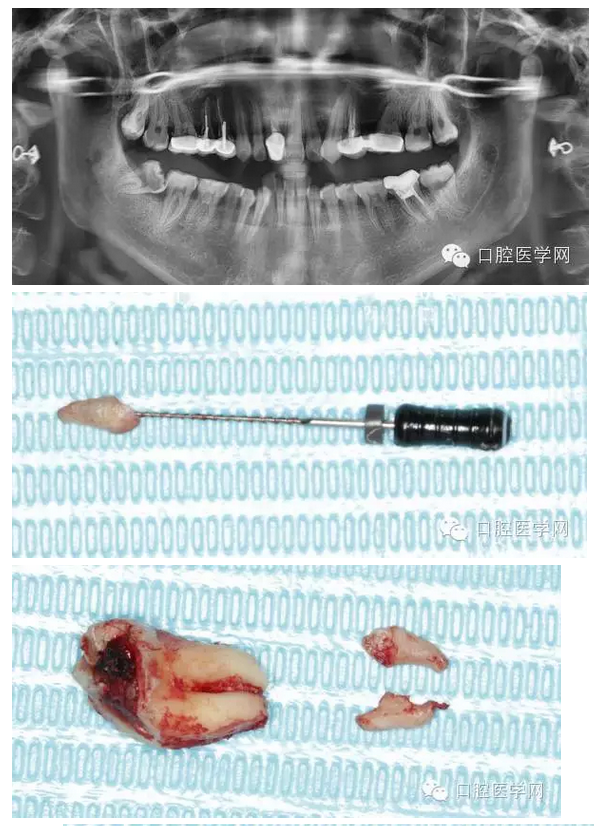

檢查發(fā)現(xiàn)右下8近中前傾阻生,合面大面積齲壞。拍全景片顯示右下8根尖向近中彎曲,右下7遠中有淺齲,遠中頸部有骨缺損。

拔牙過程就不贅述了,果然斷根了,于是用40號H銼插入牙根斷面的根管口里,并盡量擰緊,然后拔出。最近好像買不到碧藍麻,只有斯康杜尼,局部浸潤麻醉后出血明顯,嚴重影響操作,為了找根管口,擦拭了N個小棉球,讓人不堪忍受!讓人懷念的碧麻啊!